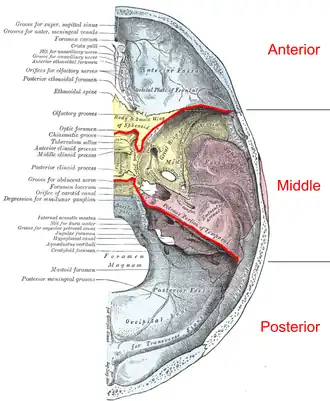

Base of the skull. Upper surface. (Middle cranial fossa is the centermost of the three indentations, in pink and yellow.) | |